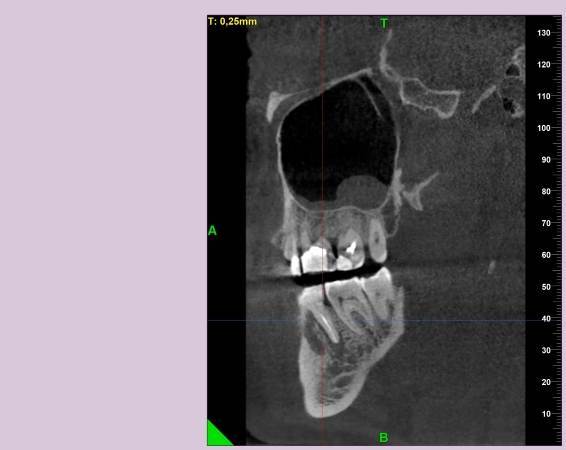

КТ от 28.05.2024

28_05.24(2).jpg.0ffa1febe861106733e1de830afbe6f4.jpg28_05.24-1(2).jpg.9c45d7be16aeed505bd413ce9bc6e69e.jpg28_05.24-2.jpg.a728a7d7e6213c1c8302b43adc89e4d0.jpg28_05.24-4(2).jpg.ac43f3448a3988c7006f74e1d0ce09da.jpg28_05.24-6(2).jpg.dd1fd85c6cc0fcd3d43bd9e71fc0d616.jpg28_05.24-8(2).jpg.885c8cb905445e9308f124fb9e5c616b.jpg28_05.24-9(2).jpg.6cceaaaa1b56d0967482c87b951fbe2d.jpg28.5.24-5(2).jpg.b2d79427a16769c9fd4f0d0911a9db8f.jpg28.5.24-7(2).jpg.f6c17f9820e72dc2708955a65a190b57.jpg28.0524-3(2).jpg.0aa9f153071766a340b428158a94ade8.jpg

Лекарство было извлечено, и каналы запломбированы гуттаперчей. Доктор предупредила, что зуб будет болеть, и прийти я должен после того, как зуб "успокоится", болевые ощущения пропадут. На третий день десна под зубом вспухла, и начала сочиться сукровица. Я решил сделать новое КТ(28.05.2024), и с результатом сходить в другие клиники для консультации. В первой мне сказали, что доктор не должна была начинать лечение, потому, что зуб идет под удаление. Во второй клинике, что попытаться вылечить можно, но изначально были допущены ошибки в лечении, и надо переделывать.

Что-то можно сделать с 46 зубом для сохранения, или он должен быть удален?